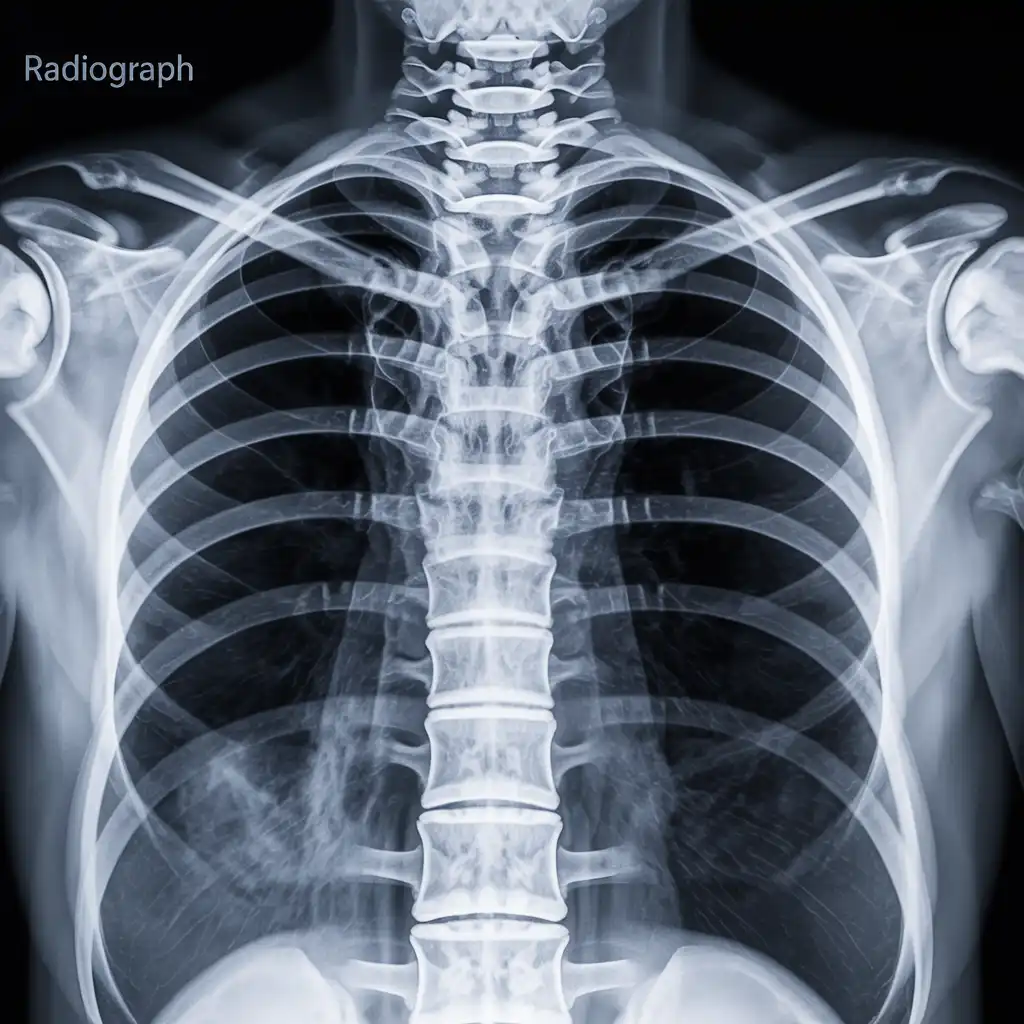

Una radiografia a domicilio è un esame radiologico eseguito da un tecnico specializzato che viene a casa tua con apparecchiature digitali portatili. L’esame si svolge sul posto, senza spostare il paziente e con la stessa qualità di una struttura ospedaliera.

Dopo l’acquisizione delle immagini, queste vengono inviate al medico radiologo che referta rapidamente e ti invia tutto in formato digitale. Un servizio comodo, sicuro e ideale per chi ha difficoltà negli spostamenti.